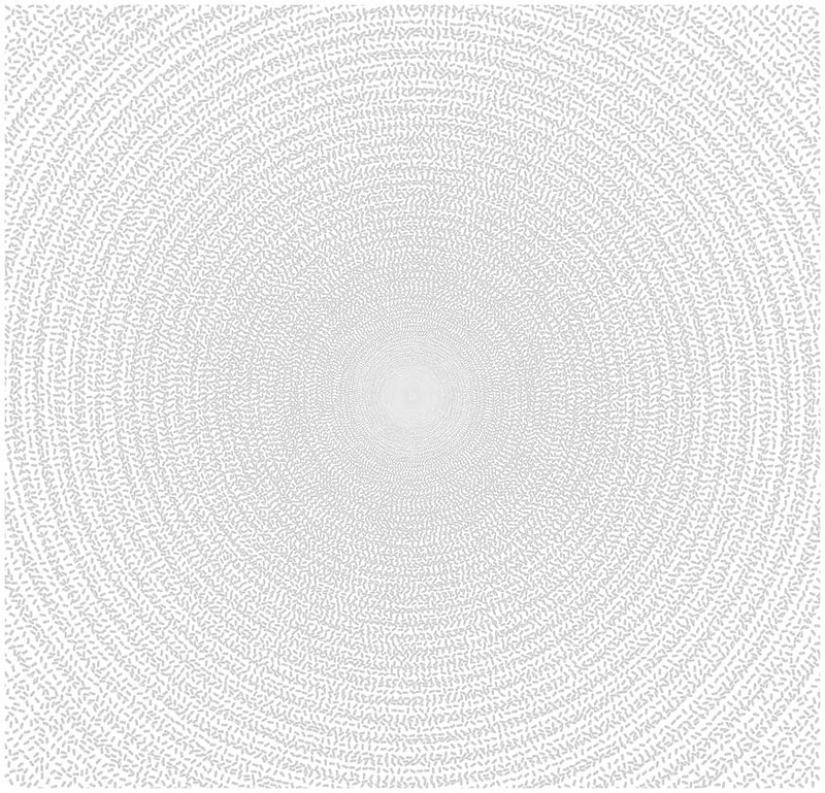

31. 213 thousand tablets of the narcotic painkiller Vicodin (known for the TV series "Dr. house") – is equal to the number of annual ambulance trips in the US on the challenges associated with the use and abuse of pain relievers.